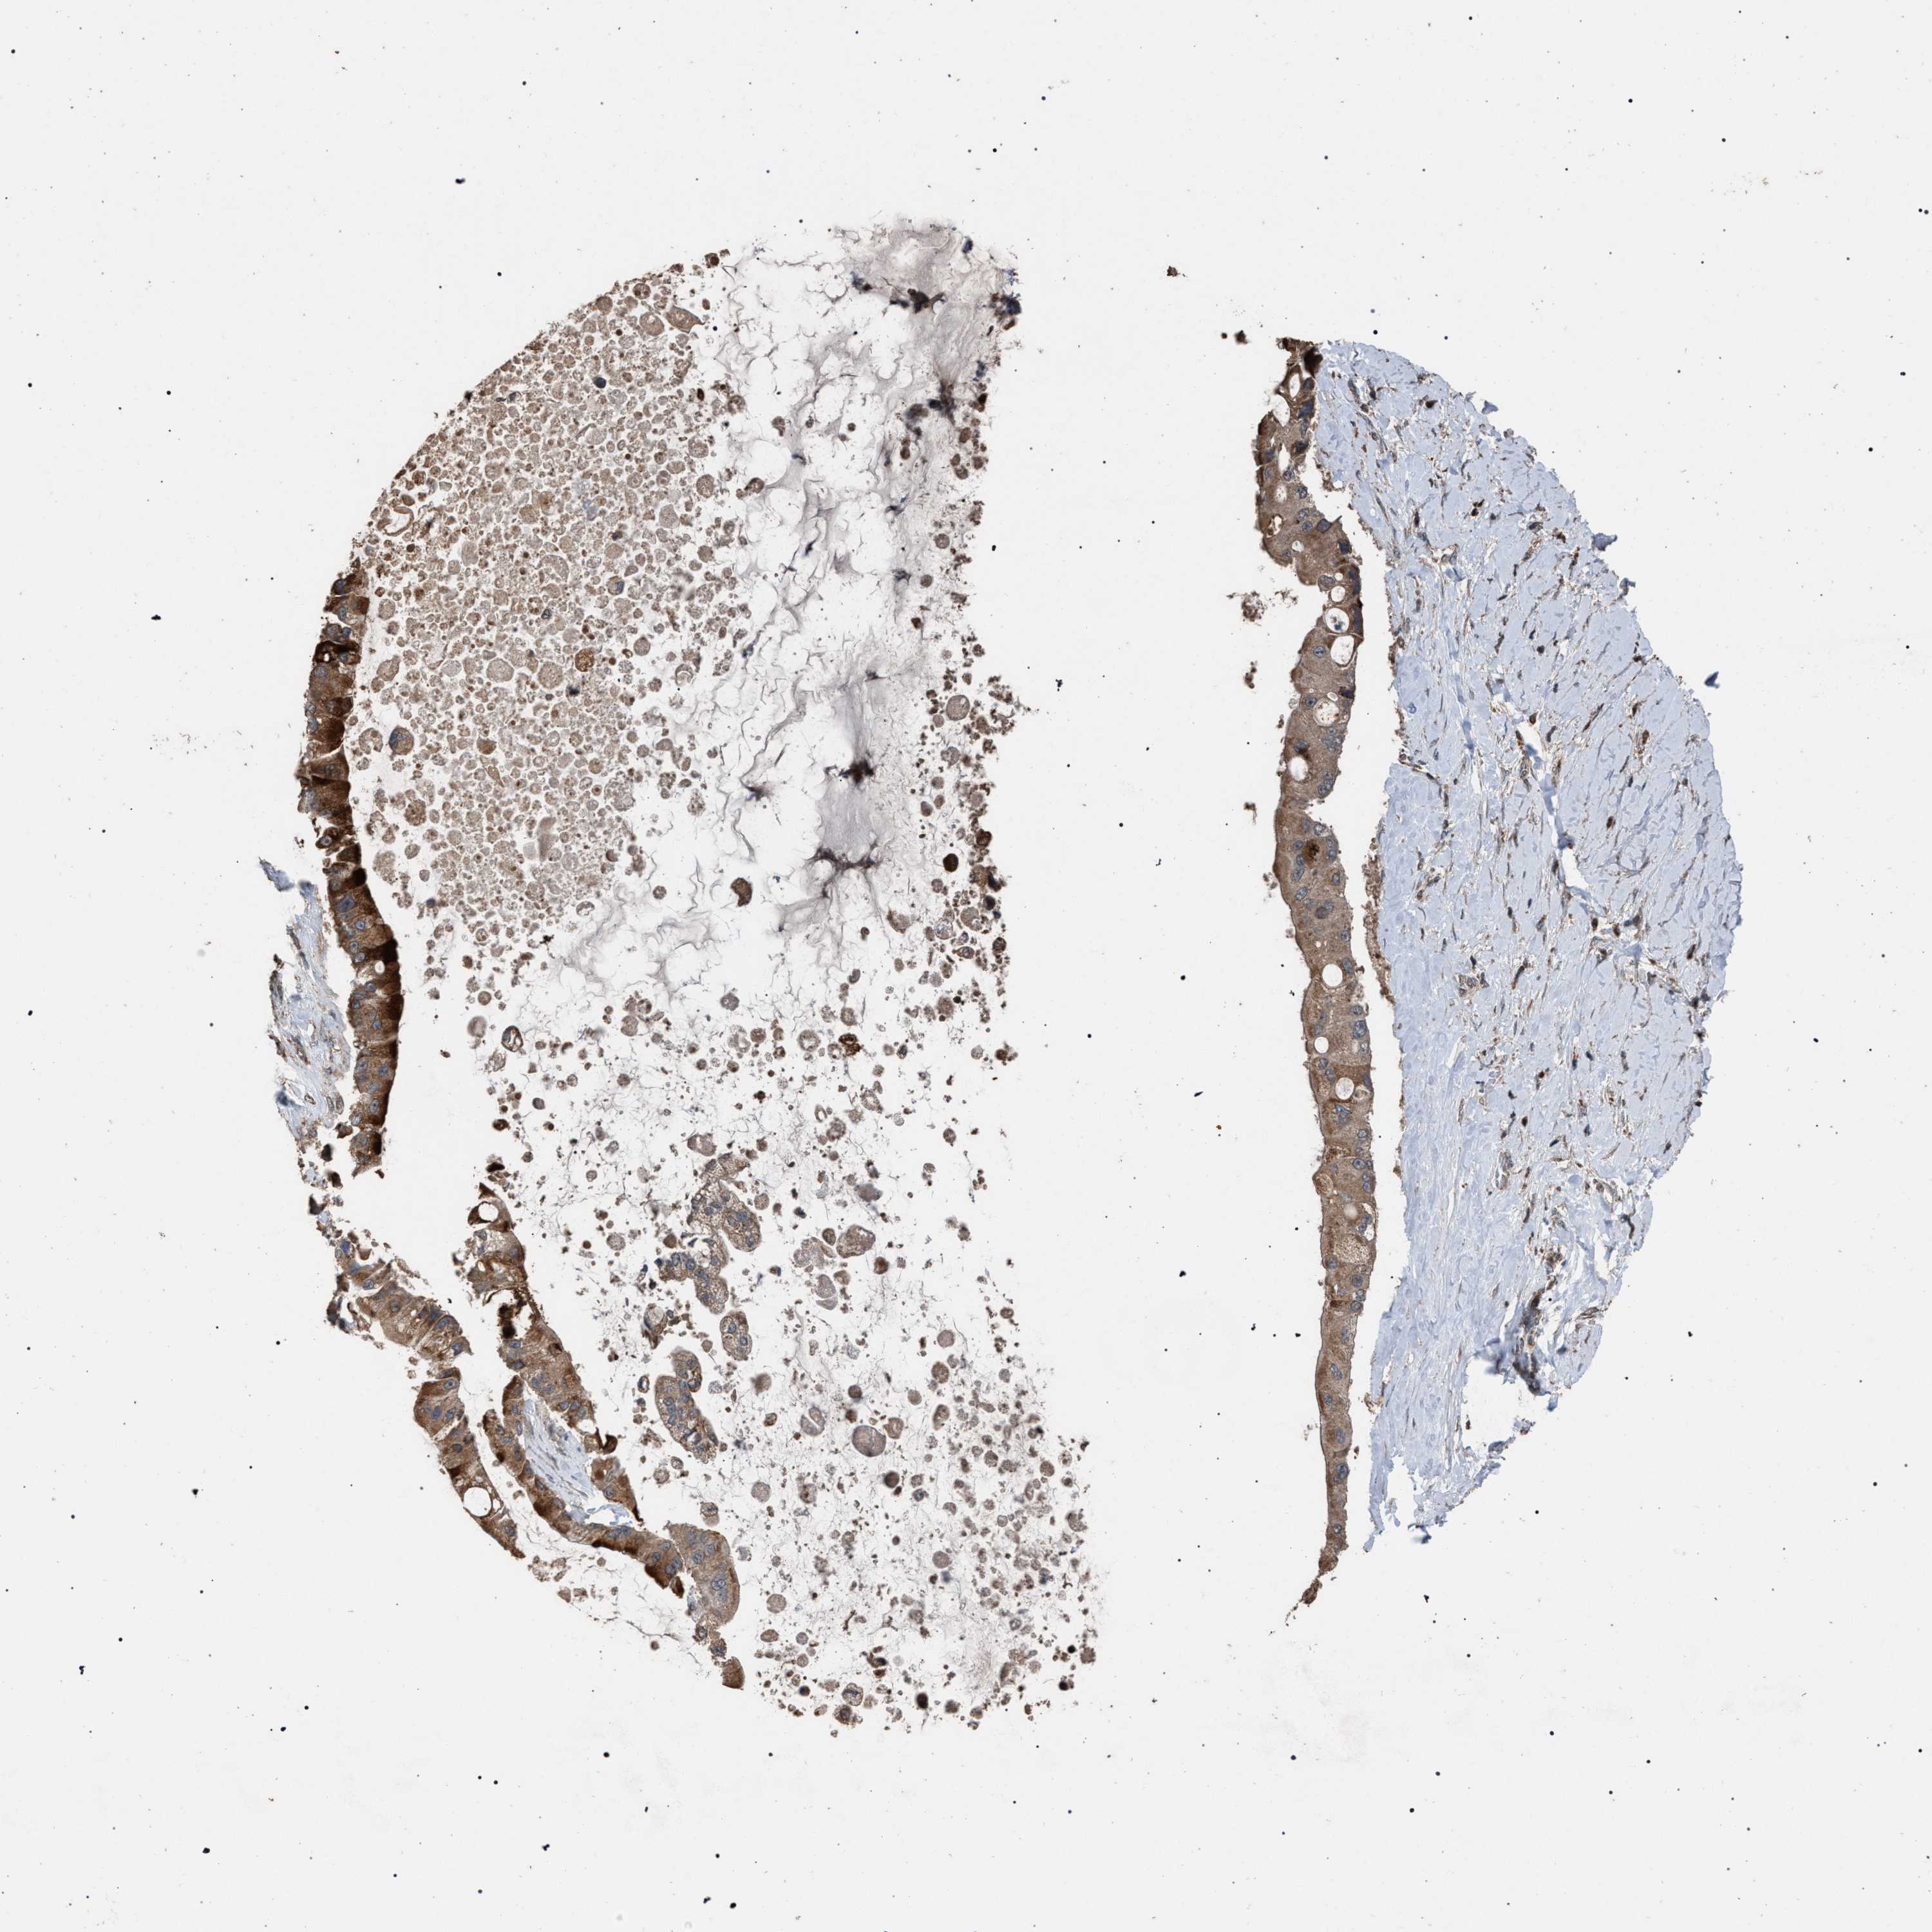

LIVER CANCER - Protein expressioni

A mouse-over function shows sample information and annotation data. Click on an image to view it in a full screen mode. Samples can be filtered based on level of antibody staining by selecting one or several of the following categories: high, medium, low and not detected. The assay and annotation is described here.

Note that samples used for immunohistochemistry by the Human Protein Atlas do not correspond to samples in the TCGA dataset.

Antibody stainingi

Antibody staining in the annotated cell types in the current human tissue is reported as not detected, low, medium, or high, based on conventional immunohistochemistry profiling in selected tissues. This score is based on the combination of the staining intensity and fraction of stained cells.

Each image is clickable and will lead to virtual microscopy that enables deeper exploration of all samples and also displays staining intensity scores, fraction scores and subcellular localization as well as patient and tissue information for each sample.

Antibody HPA021547

Staining

High

Medium

Low

Not detected

Intensity

Strong

Moderate

Weak

Negative

Quantity

>75%

75%-25%

<25%

None

Location

Nuclear

Cytoplasmic/membranous

Cytoplasmic/membranous,nuclear

Cholangiocarcinoma

Carcinoma, Hepatocellular, NOS